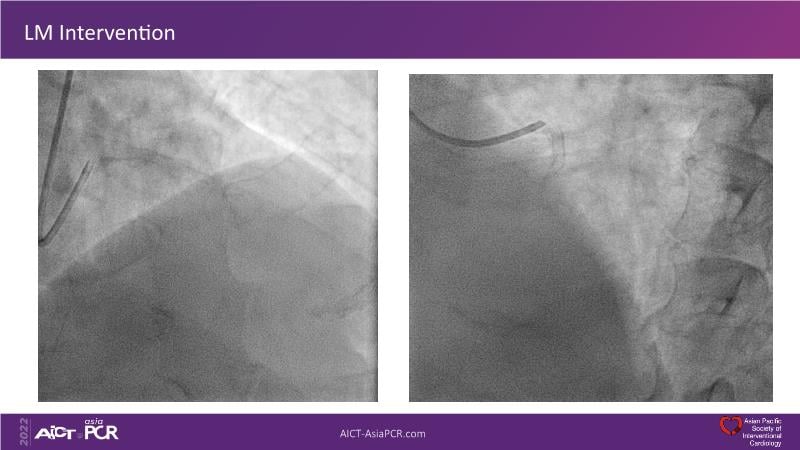

In this session, presenters describe how to use IVUS and physiology in the assessment of left anterior descending and/or left circumflex ostium in distal left main disease. Discover in the second part the general principles and clinically validated strategies for ultralow contrast coronary angiography and zero contrast percutaneous coronary intervention.

- To learn to use IVUS and physiology in assessment of left anterior descending and/or left circumflex ostium in distal left main disease

- To learn how imaging can help with strategising left main PCI, plaque preparation, device sizing and optimising results